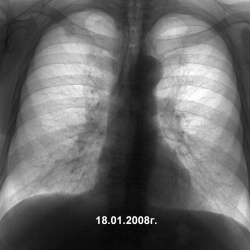

Загрузил файлы на DICOM сервер, за номером 20110224.Пациентка пришла на КТ легких с "верифицированным" саркоидозом... Впервые попала на КТ почти 2 года назад. С тех пор динамика в легких...